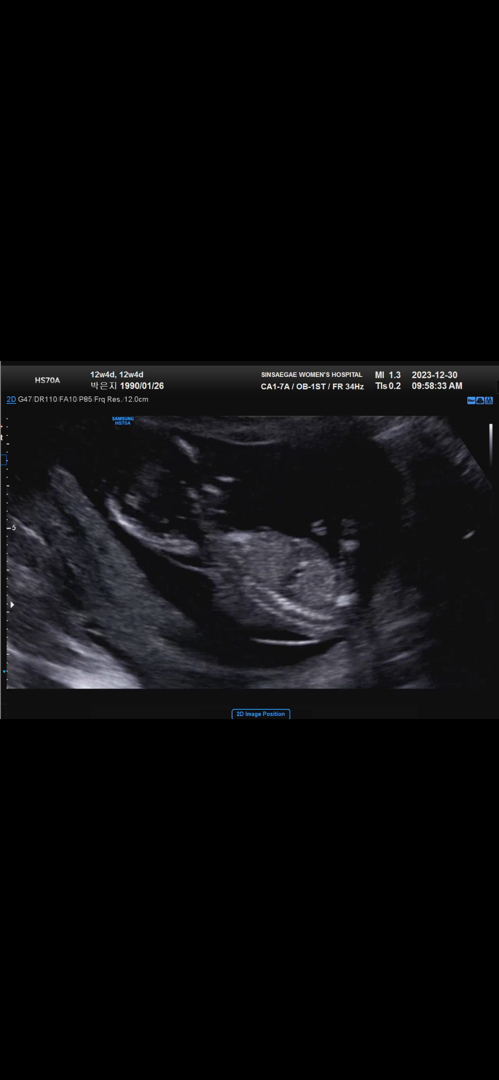

요 사진으로도 성별알수있을까요?

다음주에 16주검진가는데 딸 아들 상관없이 기다리고있는데 주변에서 하도 성별을물어봐서 조금 궁금해지기 시작해져요ㅎㅎ 12주 사진으로도 알수있을까요??ㅎㅎ